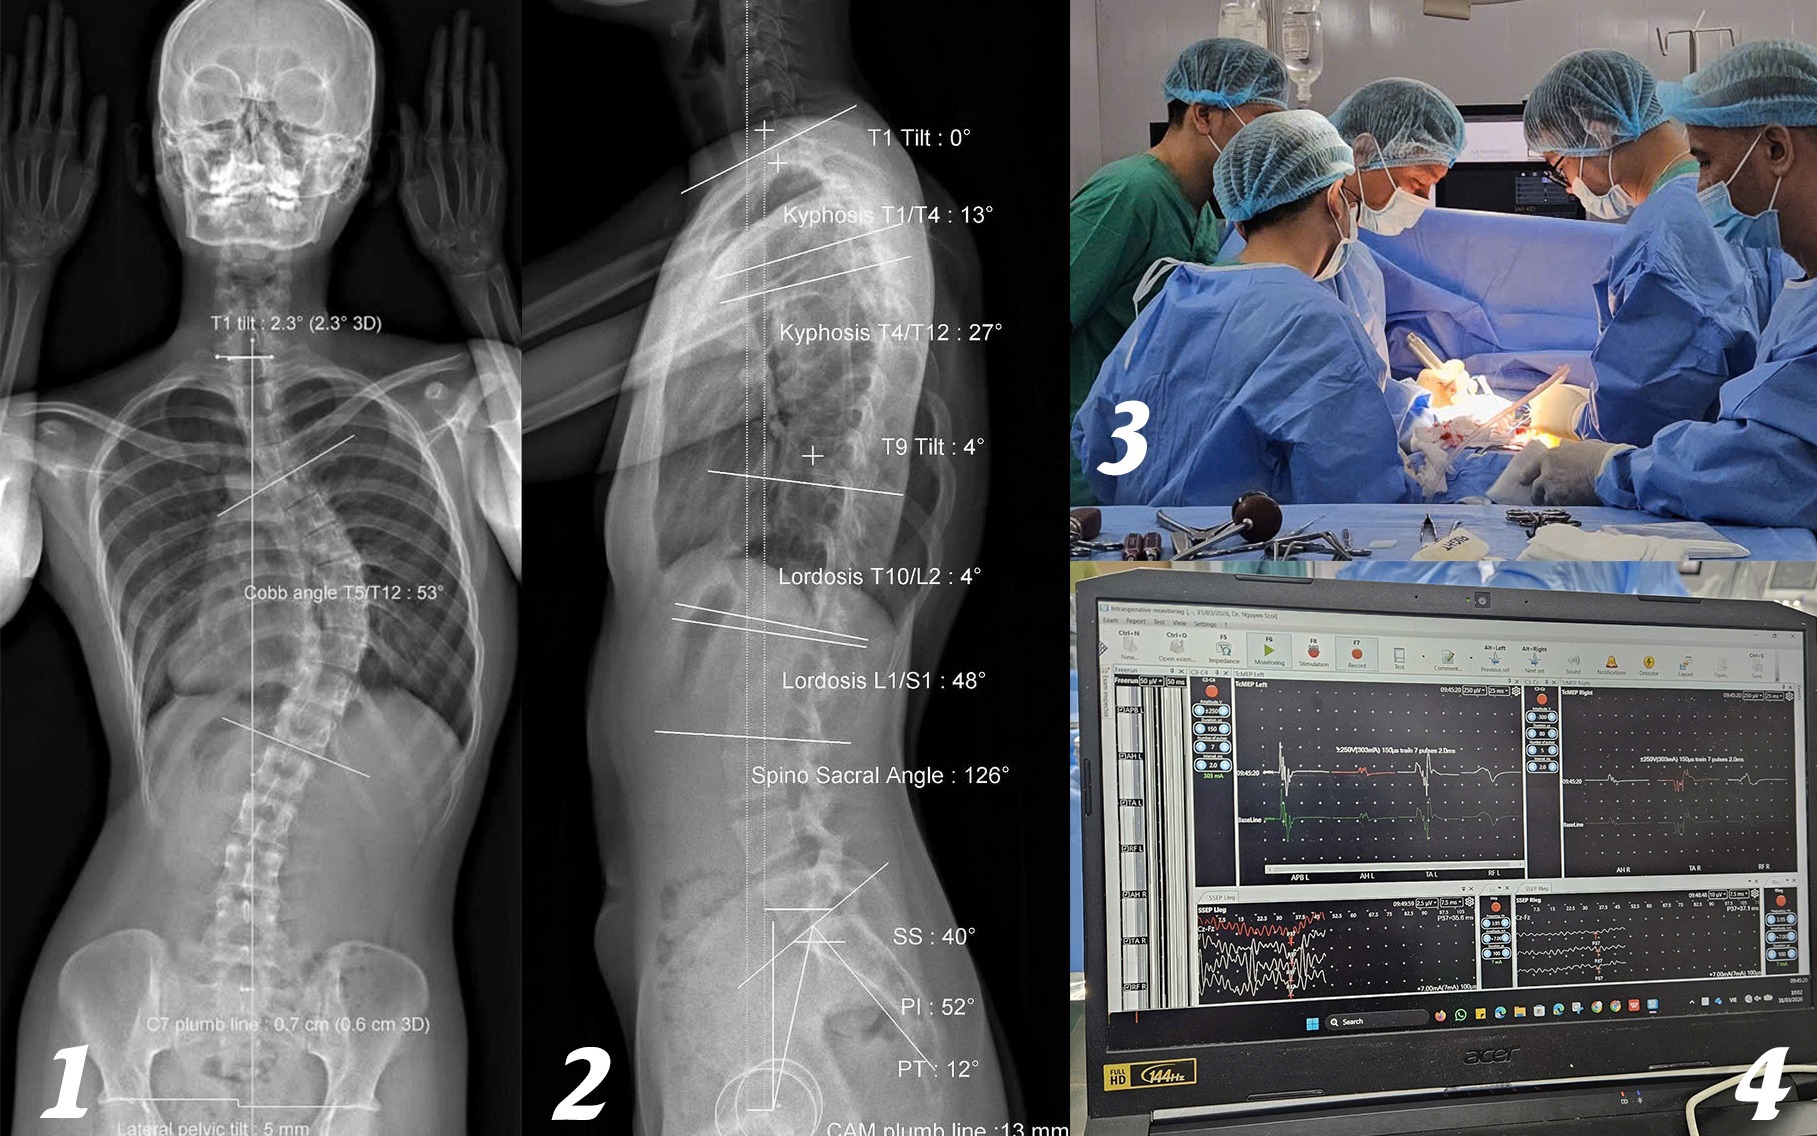

Cô gái soi gương thấy lưng có dấu hiệu lạ, không ngờ cột sống đã cong 53 độĐỌC NGAY